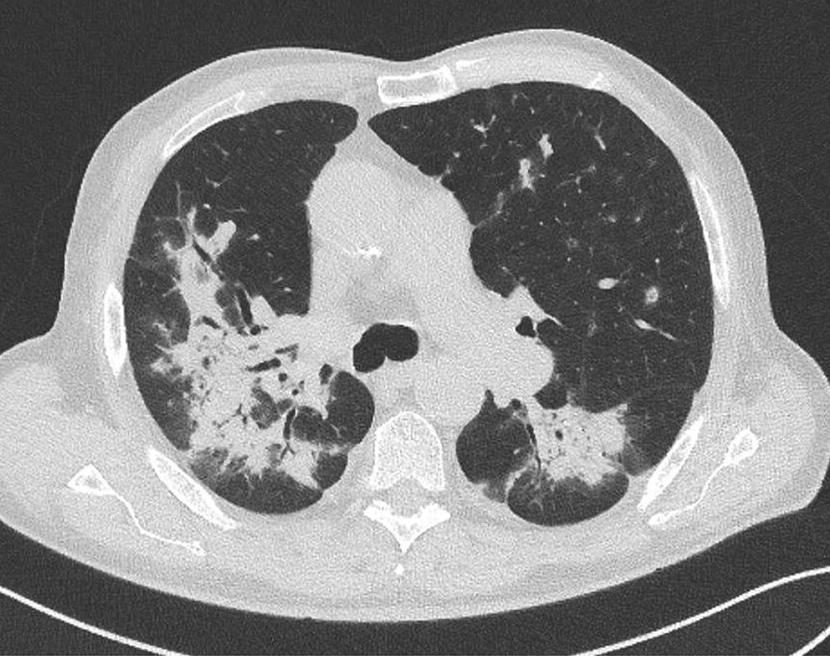

Bilde 1: Hyperdensiteter (blod) i basale cisterner og utspente temporalhorn er kjennetegn ved CT-scanning av en SAH med hydrocefalus.

CT caput er den raskest tilgjengelige og beste initiale diagnostiske test ved spørsmål om aSAH. Sensitiviteten til CT forblir svært høy for å avdekke blod i subaraknoidalrommet de første 3 døgn etter iktus (11) (Bilde 1).